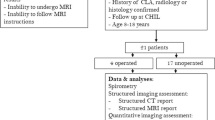

For this cross-sectional, single-center pilot study, we searched the local picture archiving and communication and hospital information systems for reports mentioning congenital lung malformation, CPAM, bronchopulmonary sequestration, congenital emphysema or bronchogenic cyst as indications for imaging and as differential diagnosis or diagnosis in patients born between the years 2008 and 2016. Inclusion criteria were (1) a postnatal, surgical malformation resection, with histologically confirmed congenital lung malformation, (2) age between 4 and 18 years, and (3) the ability to perform pulmonary function testing and to tolerate a non-sedated MRI. The exclusion criterion was an isolated extrathoracic malformation. The study was approved by the local Ethics Committee, and parents or caregivers provided written informed consent. Multiple breath washout, fractional exhaled nitric oxide, body plethysmography and spirometry and structural and functional lung MRI were performed in order on the same day.

From an initial 73 screened patients, 13 met the inclusion criteria and were contacted for study participation. Finally, five patients were enrolled. A flow diagram of the study enrollment is in Online Supplementary Material 1. The FEV1 was abnormal in three of the patients and three had an abnormal lung clearance index, while three patients had increased perfusion defects, and none had ventilation defects. A summary of the five cases, including detailed pulmonary function test results, is in Table 1. Apart from a potential reduction in the validity of the fractional ventilation maps, there was no atypical or severely reduced diaphragmatic motion demonstrated.